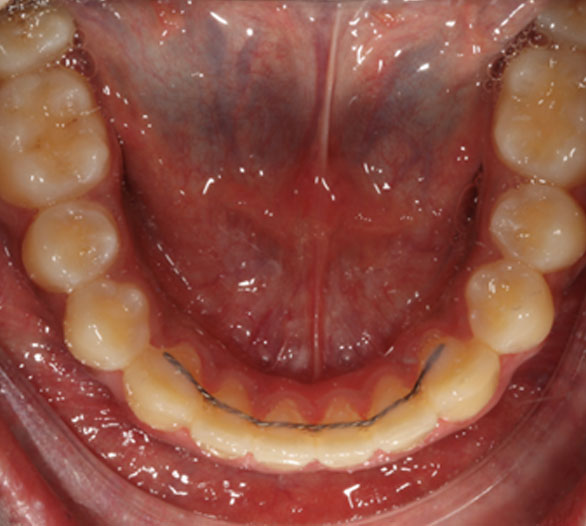

- Fixes : Fil de contention collé à l’arrière des dents antérieures pour une stabilisation permanente.